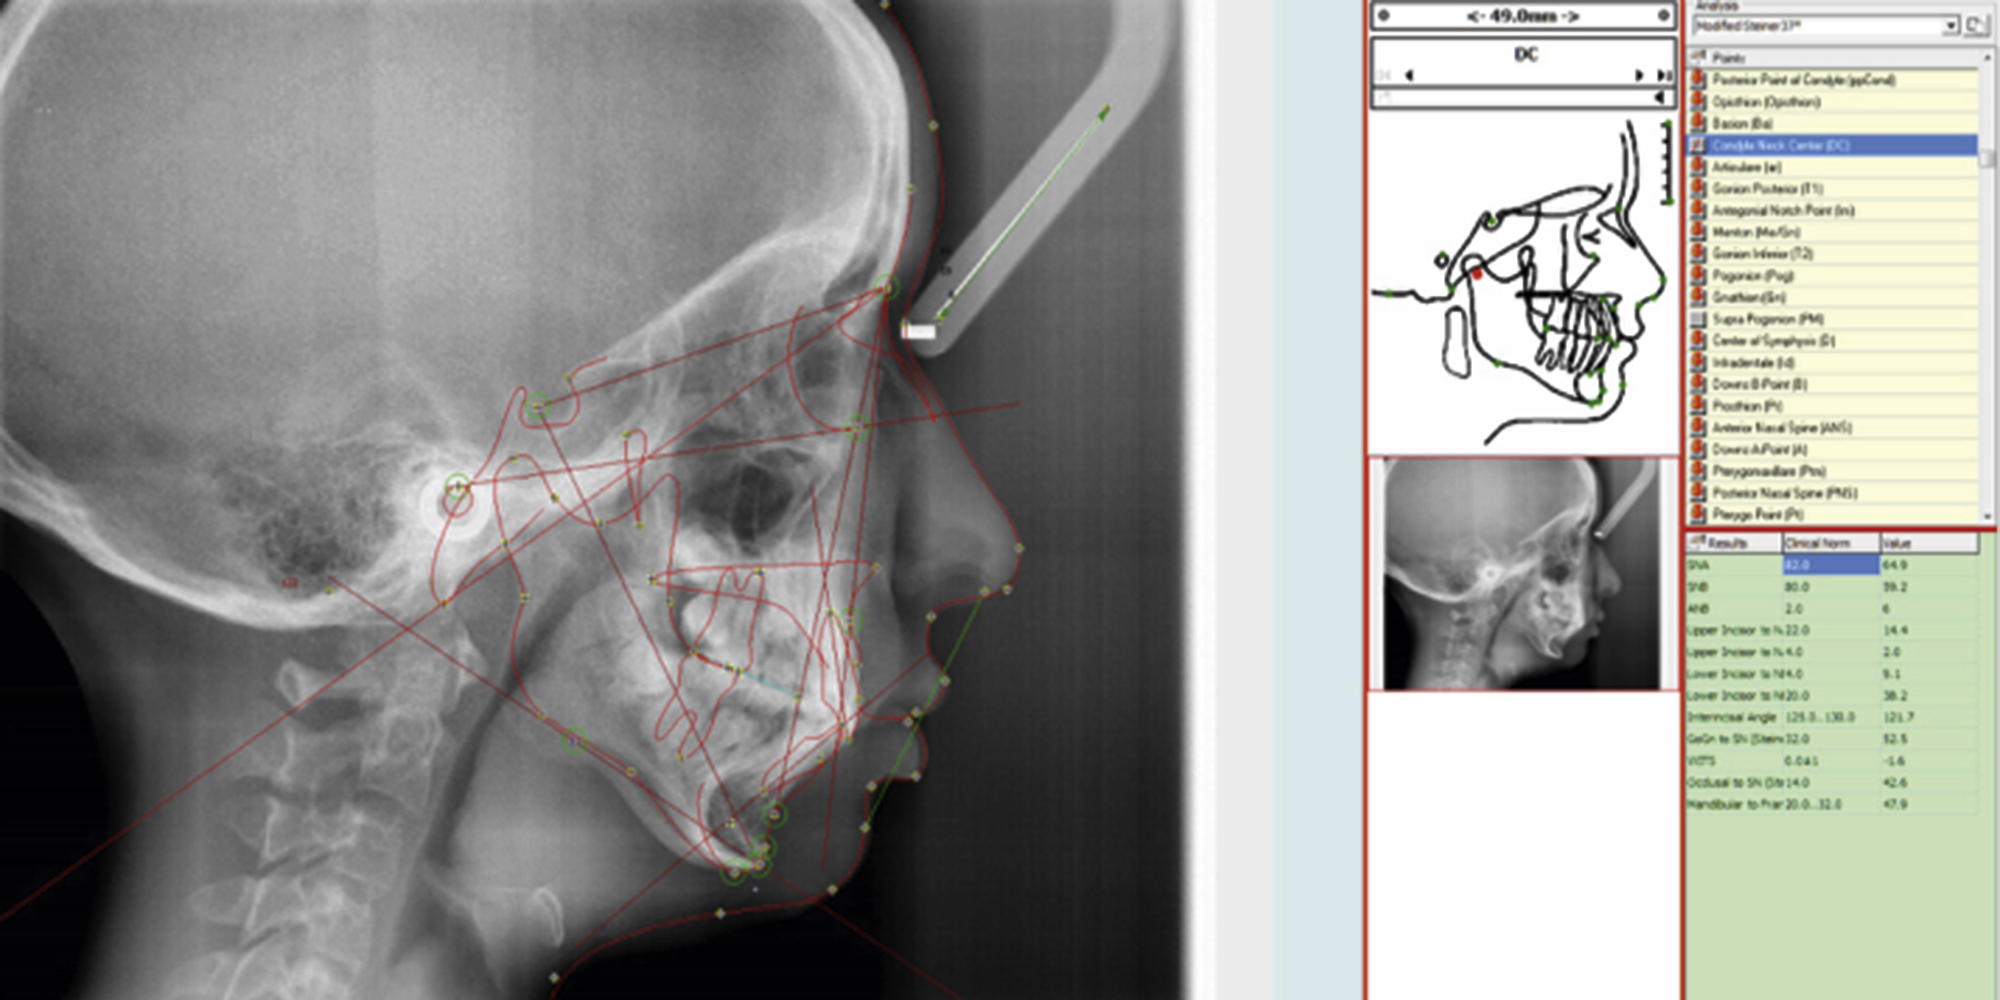

A baseline understanding of cephalometric analysis is also prudent for the operating surgeon. Various studies and analyses exist to examine the relationships of the maxilla, mandible, and skull base when viewing these structures on a lateral cephalogram. Looking at overall facial proportions, the upper facial height can be approximated measuring the distance from nasion to A point, whereas for lower facial height it is from A point from menton. The ideal facial plane is viewed by creating a vertical line, perpendicular to the Frankfort horizontal (orbitale to porion), from nasion to soft tissue pogonion. The anterior cranial base is identified as a line drawn between sella and nasion. The mandibular plane is a line drawn between gonion and menton, whereas the occlusal plane is created with a line between the maxillary and mandibular central incisors and first molars.

Other important cephalometric measurements can be evaluated when comparing the maxilla to the cranial base. This is best viewed with an angle created between the sella, nasion, and A point (SNA). The normal SNA value is 82 degrees ±3, with values greater than 85 degrees signifying a prognathic maxilla, and less than 79 degrees showing a retrognathic maxilla. The mandible is related to the cranial base by the angle between the sella, nasion, and B point (SNB). The normal SNB value is 79 degrees ±3, with a value greater than 82 degrees being consistent with a prognathic mandible, and less than 76 degrees signifying a retrognathic mandible. Chin position is evaluated by looking at the angle between sella, nasion, and pogonion (SNPg). The normal value for SNPg is 80 degrees ±3, with a value greater than 83 degrees being consistent with a protruded chin, and less than 77 degrees showing a retruded chin. A relative measure of the positioning of the maxilla to the mandible is the angle between the A point, nasion, and B point (ANB). The normal ANB value is 1–5 degrees, thus often coinciding with a class I skeletal profile. An ANB value greater than 5 degrees often coincides with a class II skeletal profile, and less than 1 degree with a class III profile , ( Fig. 21.12 ).

The upper airway can also be analyzed using cephalometric landmarks, and these values are useful when considering the potential for treating or creating obstructive airway issues with orthognathic surgery. The length of the soft palate is noted to be from PNS to P point, with a normal value of 37 mm. Values greater than this can be significant for a lengthened soft palate, and possibly naso-/oropharyngeal airway obstruction. Evidence of upper airway obstruction can also be elucidated when measuring the posterior airway space, which can be approximated with a line between the gonion to posterior pharyngeal wall (11 mm), as well as the distance from the mandibular plane to hyoid (15 mm). Lower than normal values for posterior airway space and higher than normal for mandibular plane to hyoid are consistent with airway obstruction , ( Table 21.1 ).